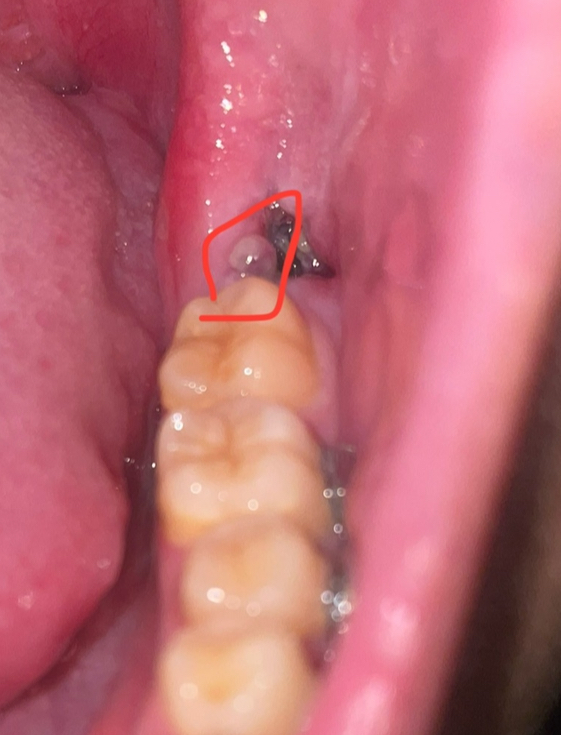

ไปผ่าฟันคุดมา แล้วมีขาวๆแบบนี้คือเป็นหนองไหมคะ

ตามภาพค่ะ มีอาการเจ็บด้วย ผ่ามาแล้ว 5 วันแล้วหายเจ็บ แต่เพิ่มาเจ็บบอีกรอบเมื่อ 2 วันที่แล้วค่ะ